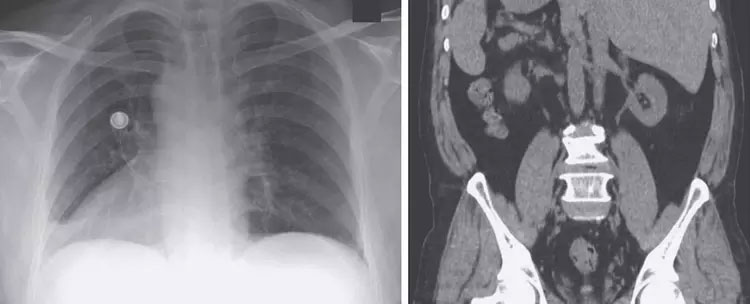

Để xác định nguyên nhân, các bác sĩ đã thực hiện chụp X-quang và nhận ra các cơ quan nội tạng của bệnh nhân đều nằm ở phía bên trái của cơ thể. Trái tim người đàn ông nằm bên phải, gan bên trái…

Hình ảnh phim chụp X-quang của người đàn ông có nội tạng đảo ngược.

Tình trạng của bệnh nhân là một bất thường bẩm sinh có tên Situs inversus. Trên thực tế, trước khi chúng ta có các công cụ chẩn đoán hiện đại, đa phần những người có bất thường bẩm sinh dạng này đều không biết được tình trạng của chính mình.

Situs inversus là một tình trạng hiếm gặp, nhưng không phải là chưa từng thấy: Donny Osmond là một trong những trường hợp nổi tiếng hơn. Trên thực tế, Situs inversus trong đó tất cả các cơ quan bụng và tim bị “phản chiếu”, là loại phổ biến nhất và có tỉ lệ 1 trên 10.000 người.